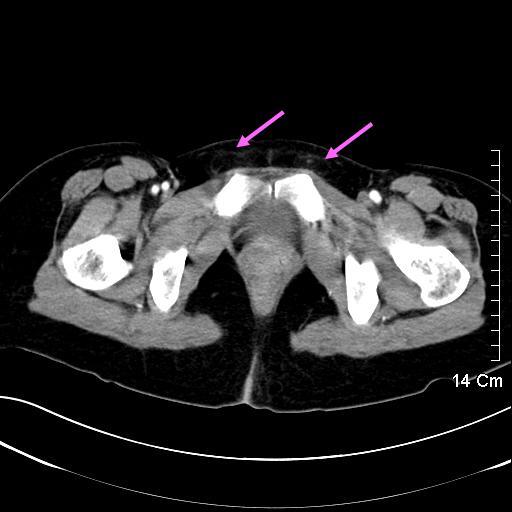

最起頭這兩張,在年輕人身上較為適用。箭頭指的地方是腹直肌,在年輕男性身上,肌肉通常會較為顯著。看看藍箭頭和粉紅箭頭,應該可以有明顯的差異。不過,要是遇上女力士或是白皙弱雞,那可能便會有顛倒的結果。

第三組影像的線索位在恥骨的兩側。藍色箭頭指出是男性的腹股溝管,裡頭有動脈、靜脈、輸精管,自然較為明顯。粉紅箭頭指的地方只有細細的圓韌帶,不甚明顯。